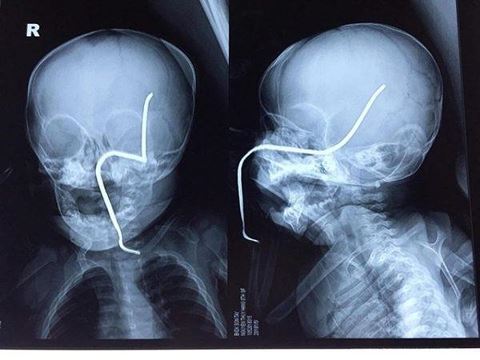

Một cháu bé mới chỉ 8 tháng tuổi đã không may bị 1 thanh sắt dài văng trúng đâm thủng sọ cháu. Nguyên nhân được cho là thanh sắt văng ra từ chính chiếc máy cắt cỏ cách đó không xa. Hiện tính mạng cháu đã an toàn và cần phải theo dõi thêm. Trong lúc đang chơi gần nhà, cháu Nguyễn T.H (8 tháng tuổi, ở Sơn Tây) không may bị chiếc máy đang cắt cỏ cách đó khoảng 15m vô tình làm bắn văng thanh sắt rỉ nằm ẩn dưới cỏ vào má trái, xuyên thủng hộp sọ của cháu. Cháu H. được gia đình đưa đi sơ cứu tại Bệnh viện Đa khoa Sơn Tây, sau đó chuyển lên cấp cứu tại bệnh viện Nhi Trung ương chiều 1/5.

Các bác sĩ khoa Cấp cứu – Chống độc, Bệnh viện Nhi Trung ương cho biết, cháu H. vào viện trong tình trạng kích thích, vật vã, quấy khóc, có dị vật là thanh sắt đâm xuyên thẳng vào má trái. Các bác sĩ đã tiến hành truyền dịch, truyền kháng sinh, giảm đau và tiêm phòng uốn ván cho trẻ, đồng thời làm các xét nghiệm cần thiết. Sau khi hội chẩn đánh giá tình hình, đêm 1/5, bệnh nhi được tiến hành phẫu thuật rút dị vật ra.

Theo Ths.Bs Hồ Trung Luân - Khoa Ngoại Thần kinh (người trực tiếp phẫu thuật cho bệnh nhi), ca mổ khá khó khăn do thanh sắt đâm vào gò má trái qua tổ chức phần mềm của má, đâm thủng sàn sọ, xuyên qua vùng não thái dương và vùng đỉnh sát các mạch máu lớn. “Thanh sắt cũ, giòn nên rất dễ gãy, lại nằm sát các mạch máu nên nguy cơ chảy máu trong mổ là rất lớn, đồng thời nguy cơ nhiễm trùng não, áp-xe não cũng rất cao” – BS Hồ Trung Luân cho hay.

Sau hơn 30 phút phẫu thuật, dị vật đã được gắp ra an toàn. Hiện trẻ đang được tiếp tục theo dõi sau mổ, kiểm soát tình trạng phù não, chống nhiễm trùng, chảy máu tại khoa Hồi sức ngoại.